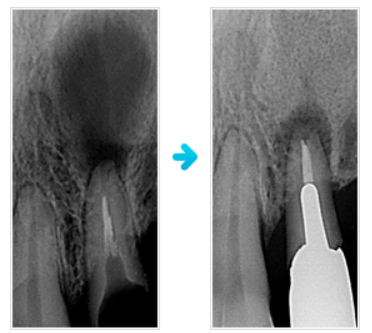

しんこう歯科での根幹治療写真の例

写真の症例では、左のように、根元に大きな影となったうみが溜まっていましたが、しんこう歯科で治療を続けて、右のように影もなくなり、骨も再生しています。

しんこう歯科では、歯の根の中をきれいにして消毒後、さらに問題となる菌や炎症を抑える根幹治療を実施しています。これらの治療は、非常に効果を発揮しており、患者様にも安心して治療を受けていただけると存じます。